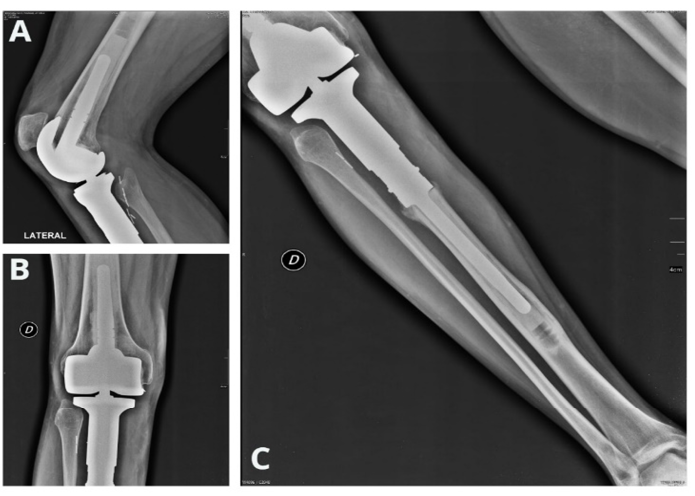

Alrededor de diez días después del anterior resultado, se le realizó un estudio de coloración en espécimen de reconocimiento y se constató un tejido óseo con compromiso por sarcoma fusocelular grado II en la tibia proximal derecha, de tamaño 7 cm., sin compromiso de tejidos adyacentes. Posterior a este diagnóstico el paciente se sometió a una cirugía con recesión del tumor y reemplazo parcial de la articulación, epífisis y parte de la metáfisis proximal de la tibia del miembro inferior derecho (Figura 1 y 2). El paciente antes de la cirugía se sometió a una sesión de quimioterapia, y luego de su intervención quirúrgica se le practicaron diez quimioterapias más, con el objetivo de que pudiera ser controlada cualquier acción metastásica.

Figura 1. Reemplazo parcial de la articulación, epífisis y parte de la metáfisis proximal de la tibia del miembro inferior derecho.

Fuente: Elaboración propia.

Figura 2. Radiografía de control del miembro inferior derecho un año después de la intervención. A. Vista lateral del remplazo parcial de la articulación. B Vista frontal del remplazo parcial de la articulación y epífisis proximal de la tibia. C. Vista frontal total del reemplazo parcial de la articulación, epífisis y parte de la metáfisis proximal de la tibia.